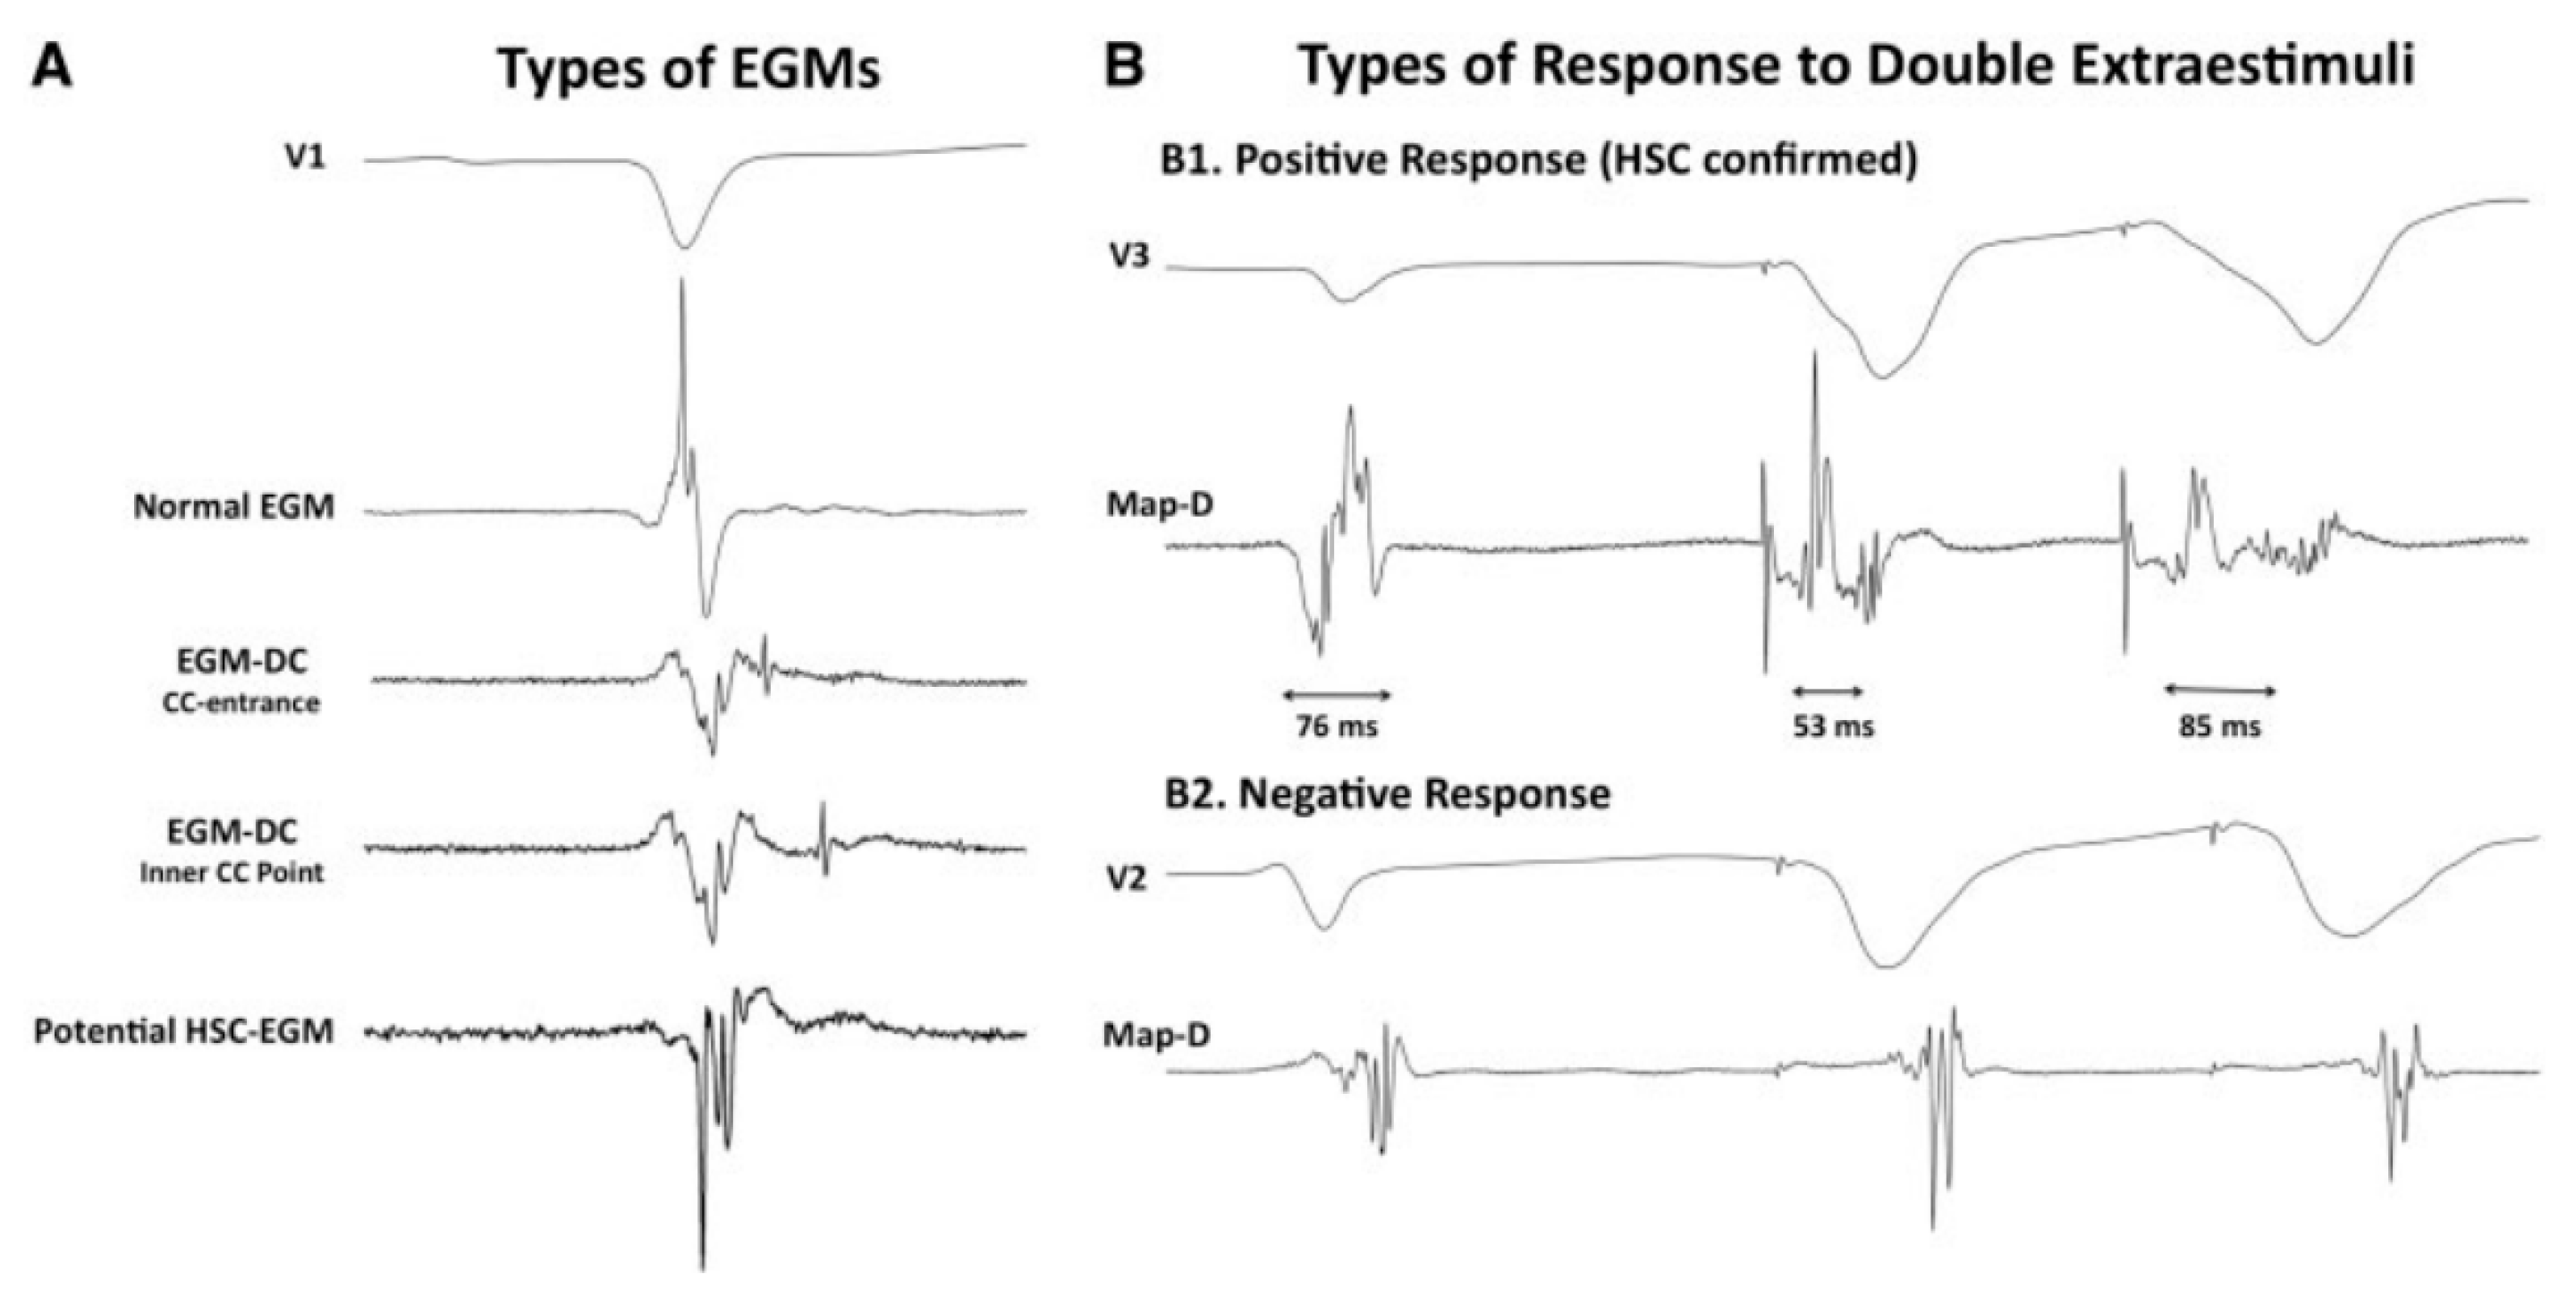

3.2. Hidden Slow Conduction (HSC) Mapping

- Acosta, J.; Andreu, D.; Penela, D.; Cabrera, M.; Carlosena, A.; Korshunov, V.; Vassanelli, F.; Borras, R.; Martínez, M.; Fernández-Armenta, J.; et al. Elucidation of hidden slow conduction by double ventricular extrastimuli: A method for further arrhythmic substrate identification in ventricular tachycardia ablation procedures. Europace 2016, 20, 337–346. [Google Scholar] [CrossRef]

- Acosta, J.; Soto-Iglesias, D.; Jáuregui, B.; Armenta, J.F.; Penela, D.; Frutos-López, M.; Arana-Rueda, E.; Pedrote, A.; Mont, L.; Berruezo, A. Long-term outcomes of ventricular tachycardia substrate ablation incorporating hidden slow conduction analysis. Heart Rhythm 2020, 17, 1696–1703. [Google Scholar] [CrossRef]

- Riva, M.D.; Naruse, Y.; Ebert, M.; Androulakis, A.F.A.; Tao, Q.; Watanabe, M.; Wijnmaalen, A.P.; Venlet, J.; Brouwer, C.; Trines, S.A.; et al. Targeting the Hidden Substrate Unmasked by Right Ventricular Extrastimulation Improves Ventricular Tachycardia Ablation Outcome After Myocardial Infarction. JACC Clin. Electrophysiol. 2018, 4, 316–327. [Google Scholar]